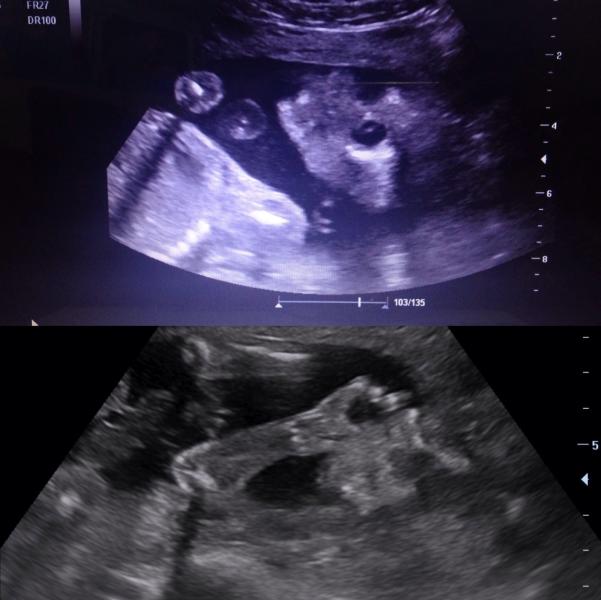

Ураааа🎉у нас будет доченька!!!😍Как мы все и хотели 👸🏼 Были с мужем сегодня в МЦ "Здоровье" у Серебренниковой В.Ю.👍очень она нам понравилась, добрая, внимательная, всё рассказала и показала, 45 минут аж смотрела. За это время наша малышка, что только не делала😄зевала, махала нам ручкой👋🏼тёрла глазки, крутилась во все стороны, успела даже покушать, т.к. к концу узи желудочек её наполнился. А как она мило сосала ручку☺️Ой девочки, я просто умиляюсь с этих видео роликов! Смотрю без остановки. Всё скинули нам на флешку. Еще послушали её сердцебиение❤️Весим мы уже 400 гр💪🏼все органы развиты правильно, все данные по норме и еще у нас тонкая талия💃в маму))) так же посмотрели узи в 3D. Вообщем, впечатлений и эмоций море!!!😝 P.S. Фото понятны наверно только мне)) уж больно она крутилась и записали нам всё в видео.

Я тоже у нее на узи была))) и тоже видела как сосет пальцы:)) фото такие же